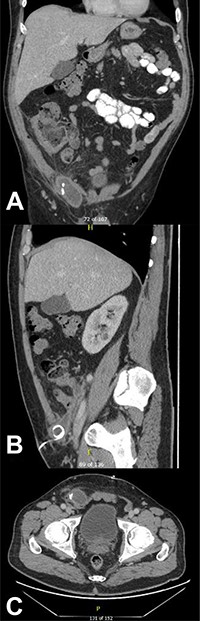

CT of the abdomen and pelvis demonstrating a fluid collection/abscess extending into a right inguinal hernia sac in (A) coronal (B) sagittal and (C) apical planes.

He had ongoing episodes of fever (38.1, 38.8 and 38.5°C) on days 3 and 4 post-operatively, so his antibiotics were escalated to piperacillin/tazobactam and metronidazole, according to microbiologist advice. However, on day 5 post-operation, he was still complaining of a severe tenderness on the right iliac fossa, associated with guarding, he was diaphoretic and febrile and clinical examination showed a tender lump in the right inguinal region. A CT of the abdomen and pelvis was performed to assess for a deep-seated collection, and it showed post-operative changes in the right lower quadrant at the site of recent appendicectomy, with small foci of poorly encapsulated fluid in the right lower quadrant with a further more well-defined 7 cm fluid collection/abscess extending from the right lower quadrant into a right inguinal hernial orifice and extending into the hernia sac (Fig. 2).